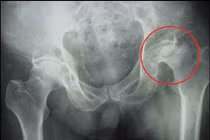

Bị hoại tử chỏm xương đùi 2 bên giai đoạn cuối, nam thanh niên 46 tuổi (Hà Nội) nhiễm HIV phải bò để di chuyển đã được các bác sĩ thay khớp háng thành công.